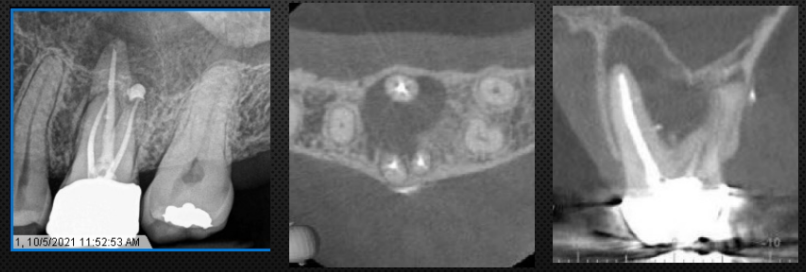

Tooth with infection usually have more bone loss (Radiolucency on the radiograph)

infection around the tooth→ more bone resorption (larger defect)